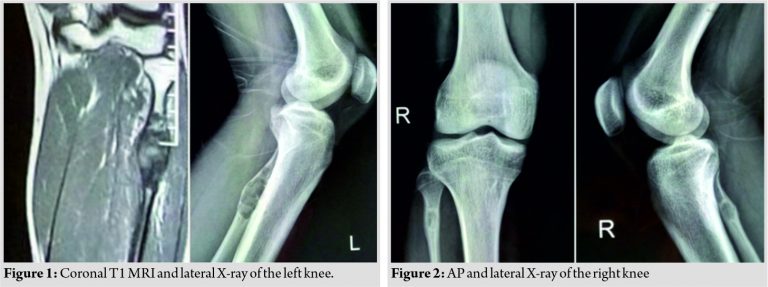

An otherwise healthy 24-year-old boy presented with a palpable mass in the region of his left proximal fibula and B/L knee pain for 6 months. He reported pain with activity, but there were no peroneal nerve symptoms. Radiographs of his left knee revealed an expansile lytic lesion at the proximal fibular epimetaphyseal level while the right knee X-ray showed a similar smaller lesion which prompted further evaluation (Fig. 1, 2). MRI was done to delineate the accurate extent of the tumor and to rule out involvement of the adjacent soft tissues (Fig. 3).